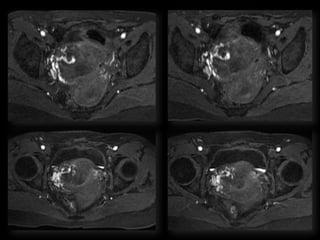

Dr. Anne Silas

HISTORY

• 40 yo female 8.5 weeks pregant

• S/P D&C for pregnancy implanted at site of

c-section scar

• 6 weeks post D&C patient presents with

heavy persistent bleeding

• For Pelvic US

• HCG = 451 mIU/mL

• What are the findings?

• What is the differential diagnosis?

• What are your recommendations?

• What is the diagnosis?

• What is the treatment?